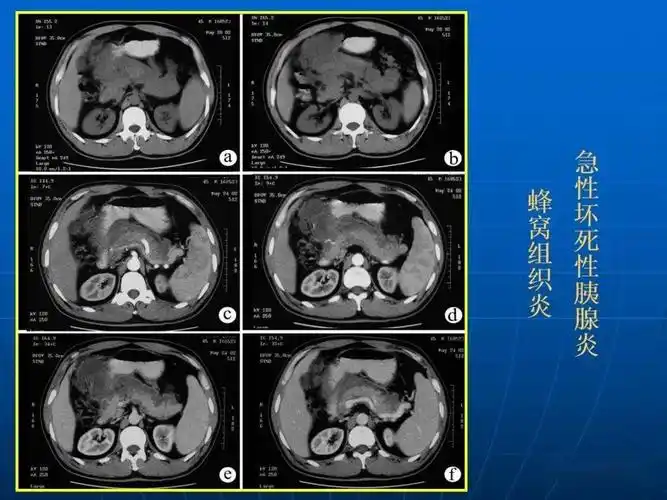

出血坏死型胰腺炎 病史: 饱餐油腻/饮酒后,上腹疼痛 ct特点: 胰腺增大